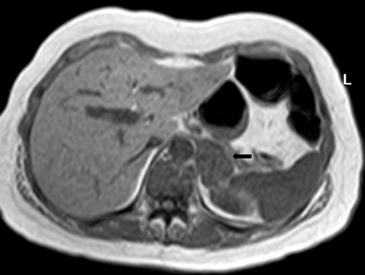

En la TC no contrastada las glándulas suprarrenales normales son homogéneas y simétricas, con una densidad muy similar a la del parénquima renal adyacente (Figura 1 a). Con un medio de contraste ev la glándula suprarrenal se opacifica en forma homogénea, similar al hígado o al bazo (Figura 1 b). Si la cantidad de tejido adiposo retroperitoneal es abundante las glándulas suprarrenales pueden aparecer enteramente rodeadas por grasa y su delimitación es más fácil (Figura 2 a); lo inverso ocurre en pacientes muy delgados con escasa grasa retroperitoneal (Figura 2 b). En RM, en secuencias ponderadas en T1 y T2 convencionales tienen una intensidad de señal homogénea, hipointensa respecto de la grasa adyacente e iso o hipointensa con respecto del parénquima hepático (Figura 3 a y b). En los cortes coronales se aprecia mejor la forma y la posición de las glándulas suprarrenales (Figura 3 c).

Figura 1. Glándula suprarrenal normal en tomografía computada. Cortes axiales de tomografía computada, donde se identifica la morfología normal de la glándula suprarrenal derecha (flecha) en fase no contrastada (a), y tras el uso de medio de contraste endovenoso (b).

Figura 3. Glándula suprarrenal normal en resonancia magnética. (a) Cortes axial ponderado en T1 la señal de la glándula normal (flecha negra) es hipointensa respecto a la grasa retroperitoneal e isointensa respecto al parénquima hepático. (b) Cortes axial ponderado en T2 en que se muestra la glándula suprarrenal derecha (flecha blanca) y (c) corte coronal ponderado en T2 en que se muestra la glándula suprarrenal derecha (flecha blanca) y la glándula suprarrenal izquierda (flecha negra) con similares características de intendidad de señal. 3. Causas y prevalencia de las lesiones suprarrenales